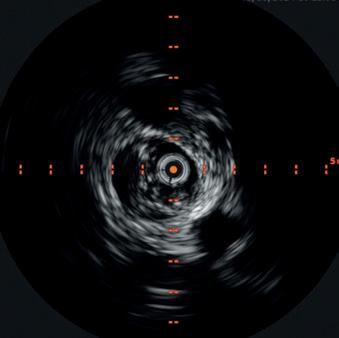

Endovascular interventions for chronic limb-threatening ischemia (CLTI) are technically demanding endeavors. Multi-level arterial disease, long-length lesions and other complex plaque characteristics are frequently encountered when treating these patients.1,2 Calcium modification with intravascular lithotripsy (IVL) has emerged as a useful tool to combat the challenges of calcified lesions with the goal of maximizing luminal gain to achieve improved endovascular outcomes, both radiographically and clinically.3 Balanced lithotripsy pulse delivery across longer-length lesions, as well as effectively treating calcified disease across multiple arterial beds, can be laborious considering the number of available pulses and the length of the IVL catheter relative to the extent of disease.

To address this, the Shockwave IVL peripheral portfolio has now been enhanced with the addition of the Shockwave E8 catheter. The Shockwave E8 contains eight emitters across an 80mm-length balloon platform with treatment diameters ranging from 2.5–6mm and the ability to deliver up to 400 pulses. A working length of 150cm now provides an extended reach for more distal disease. The Shockwave E8 catheter allows for expanded application of IVL in treating a wide range of infrainguinal disease. Longer-length lesions involving the superficial femoral (SFA) and popliteal arteries or disease involving multiple tibial arteries that may have previously required a very selective pulse delivery approach can now be more broadly treated with the Shockwave E8.

An arteriogram of the left lower extremity was performed via antegrade left common femoral artery access based on preoperative review of the lower extremity arteriogram from Uzbekistan. Scattered non-calcified plaque with moderate to high-grade stenoses were identified in the proximal and mid superficial femoral artery. Diffuse severe calcified tibial artery disease was identified. There was a long segment stenosis of the proximal and mid posterior tibial artery coupled with a more distal occlusion. The proximal peroneal artery was calcified and occluded with distal reconstitution identified. There was complete occlusion of the anterior tibial artery (Figure 2).